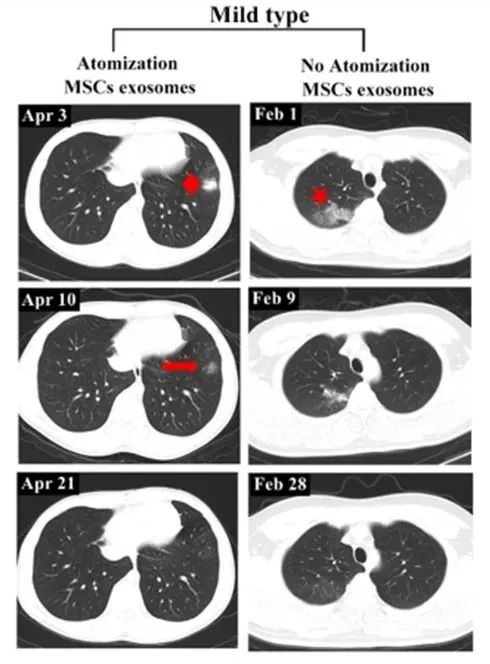

輕度病例前后影像變化:以患者 6 為例,2020 年 4 月 3 日,該患者第一次 CT 掃描顯示左肺下葉外有孤立結節(jié),4 月 4 日,患者接受外泌體霧化治療,4 月 10 日,第二次 CT 檢查顯示左肺下葉結節(jié)密度明顯降低,大小也縮小,4 月 21 日,第三次 CT 檢查,左下肺病灶完全吸收,從發(fā)現(xiàn)結節(jié)到完全吸收肺部病變所需的時間為 18 天。

相比之下,另一例患者(輕度病例,無霧化治療)類似肺部病變的吸收時間為 27 天。

左:患者 6;右:無外泌體霧化治療的輕度病例